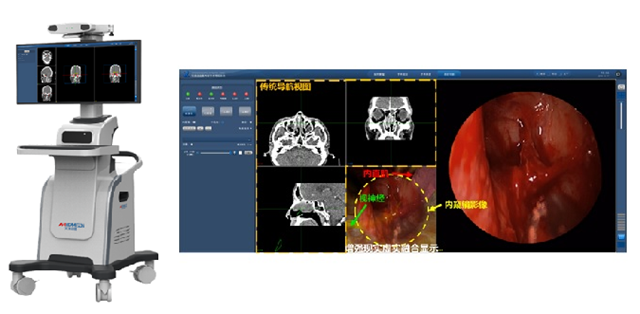

颅底外科手术导航定位系统是针对鼻腔、颅底及咽旁间隙等人体中最复杂结构外科手术的重要医疗设备。产品开发综合应用VR/AR现代高科技,通过面向术者实时提供解剖结构的位置信息进行手术导航定位,可以有效降低传统内窥镜技术容易产生并发症、术中操作方向迷失及手术失误等风险,显著提高手术的成功率,降低复发率,具有很好的临床应用价值。国内医疗需求巨大,但相关产品一直以来被国外厂商所垄断。

2013年至今,研究团队基于科技服务于人类健康的最高目标,在“十三五”重点研发计划等项目的持续支持下,对原理样机进行了不断地技术革新和优化设计,面向市场的真实要求进行产品开发,并通过一系列的标本实验、动物实验和预临床试验进行了产品的功能验证和性能完善。经过13年矢志不渝、瞄准临床应用最高目标的医疗创新产品开发,终于推出了这款国内首创、性能优于国外同类产品的颅底外科手术导航定位系统。